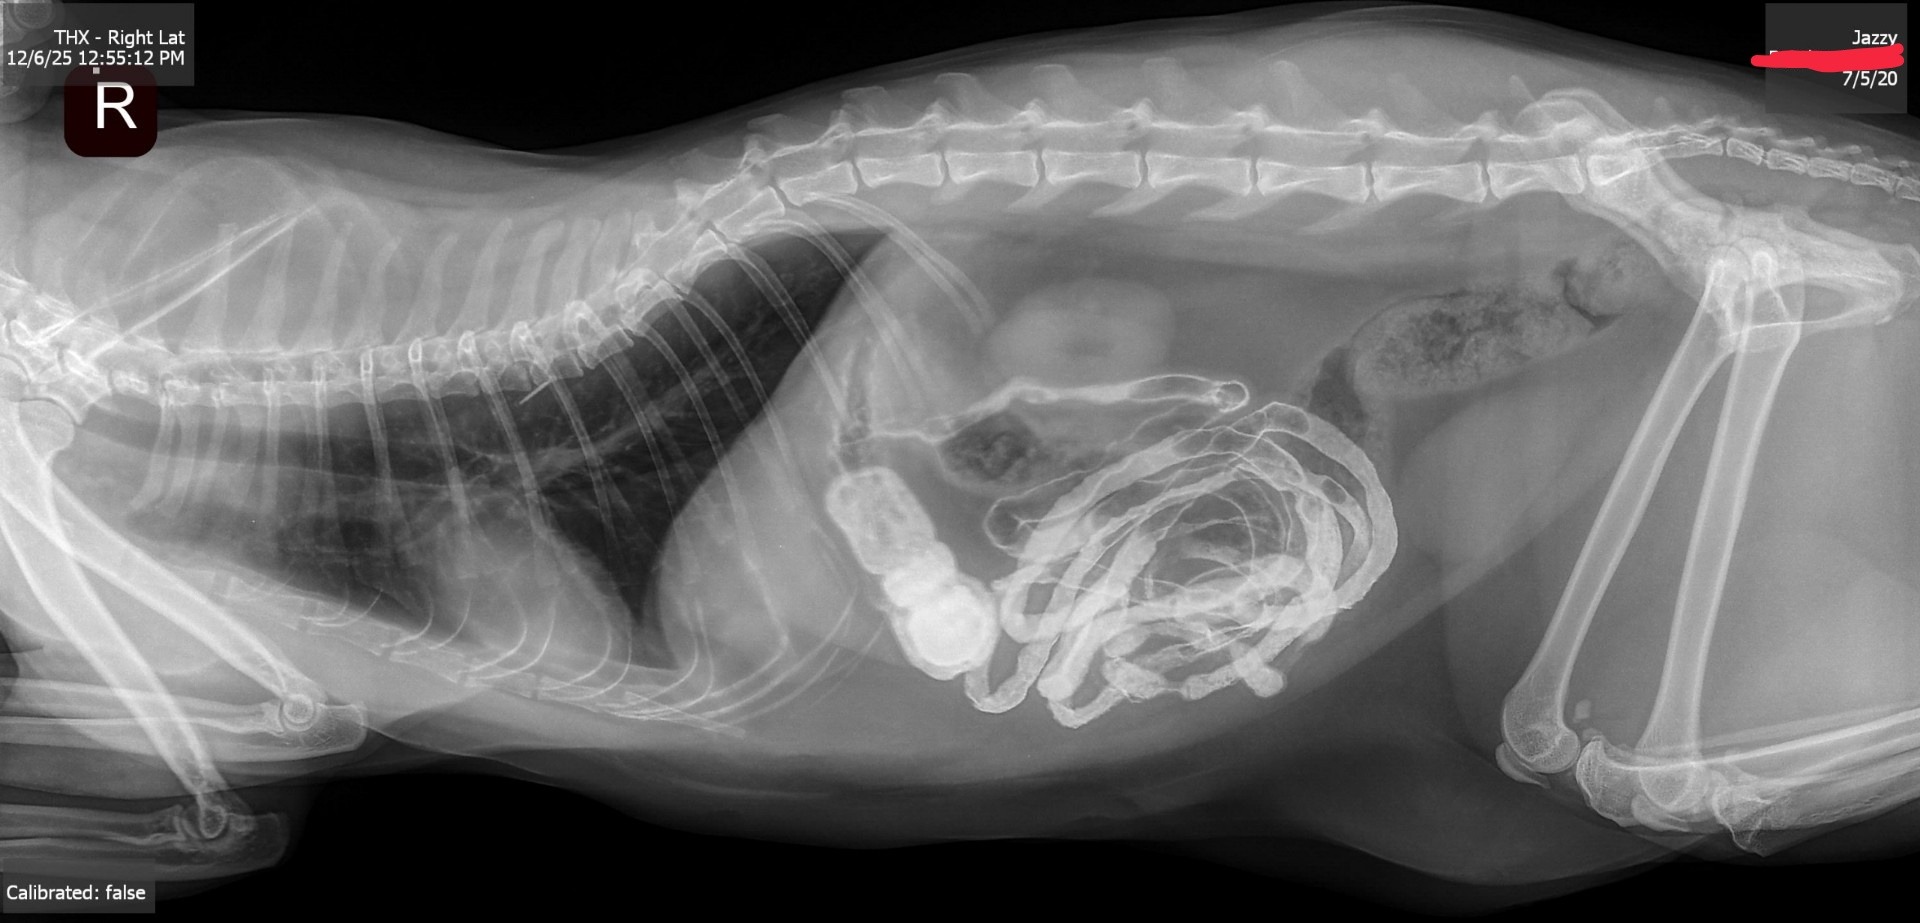

She's been throwing up a lot the past few days, and when she got an X-ray earlier today, it shows a blockage in her small intestine. We don't know what it is, but she has to get surgery.

The blood work & X-ray already cost about $600, and the surgery itself is going to be $1800. I know we're all going through a rough time economically because of all the stuff going on in the world right now.